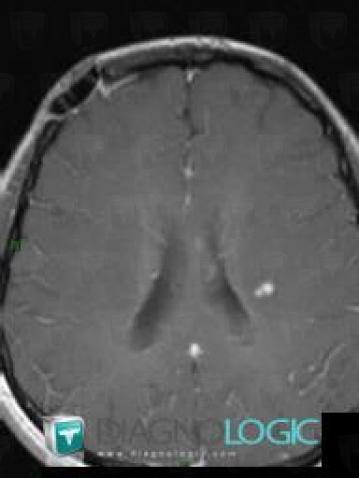

Multiple sclerosis, Cerebral hemispheres, MRI

Here is the specific information in the key image above:

- Diagnosis Multiple sclerosis, Location(s) Cerebral hemispheres, with gamuts Intracerebral lesion with moderate enhancement